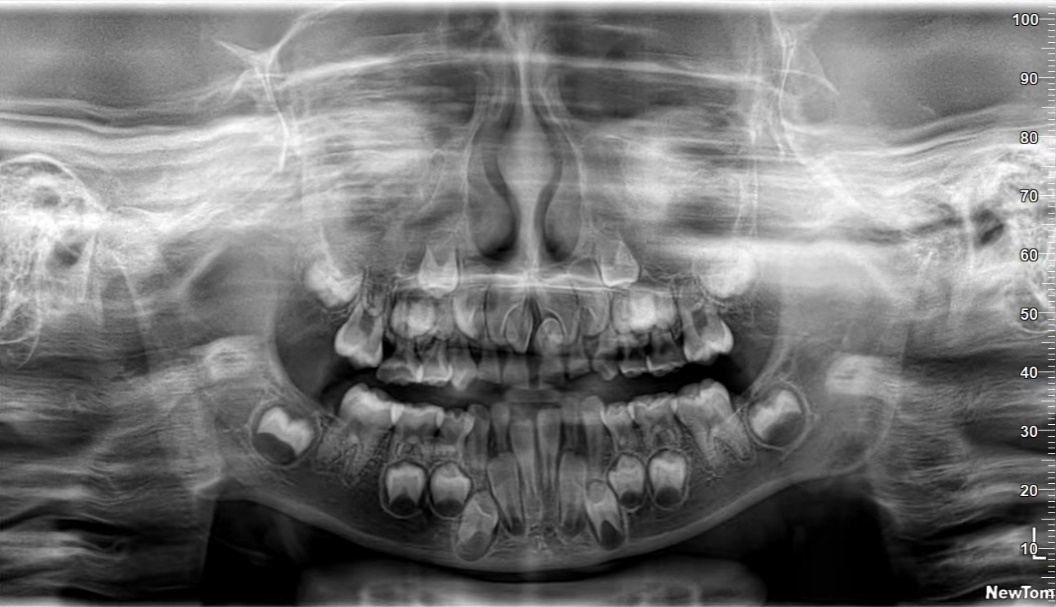

口腔曲面断层篇(全景片)

通过X线球管与胶片匣相对弧形运动,将上下颌骨的结构展示为连续的平面影像。常用于观察恒牙、乳牙龋坏情况;下颌神经管、上颌窦、上下颌骨囊肿,外伤,炎症等情况及其与周围组织的关系。

乳牙期曲面断层片,了解乳牙龋坏情况,恒牙的数目和位置,也可看到多生牙。